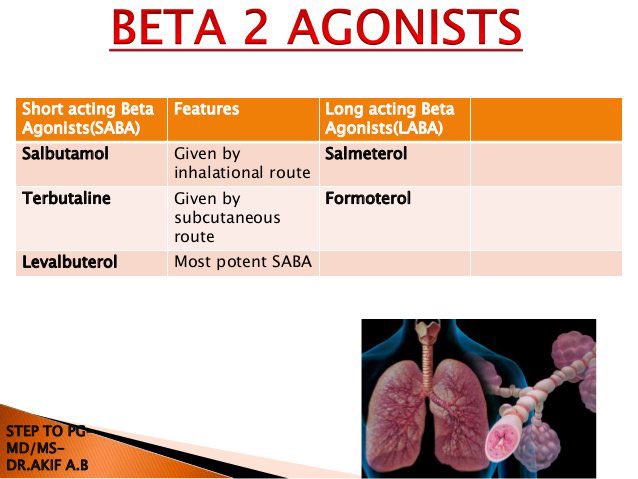

E- use SABA (short acting beta agonist )

Before Doing exercises

ليش حطيتها من ظمن اللايف ستايل لان الكثير من المصابين في الازما يعشقون الرياضه ويخافون تجيهم الاعراض فلابد انت توضح له هذي الشغله حتى لو ماسألك تفاديا حدوث نسيان لدوائه اثناء الرياضه .

E- use SABA (short acting beta agonist )

Before Doing exercises

ليش حطيتها من ظمن اللايف ستايل لان الكثير من المصابين في الازما يعشقون الرياضه ويخافون تجيهم الاعراض فلابد انت توضح له هذي الشغله حتى لو ماسألك تفاديا حدوث نسيان لدوائه اثناء الرياضه .

if symptom less than 2 days per week Will be #intermittent(before mild) & Give him: #step 1

#Step 1: SABA (short acting beta agonist )PRN

يعني احد ادوية SABA يعني عند اللزوم

👇🏻

وهنا دايما خطة الchronic تبدأ

يلا نبدأ خطة المزمن #chronic /

if symptom less than 2 days per week Will be #intermittent(before mild) & Give him: #step 1

#Step 1: SABA (short acting beta agonist )PRN

يعني احد ادوية SABA يعني عند اللزوم

👇🏻